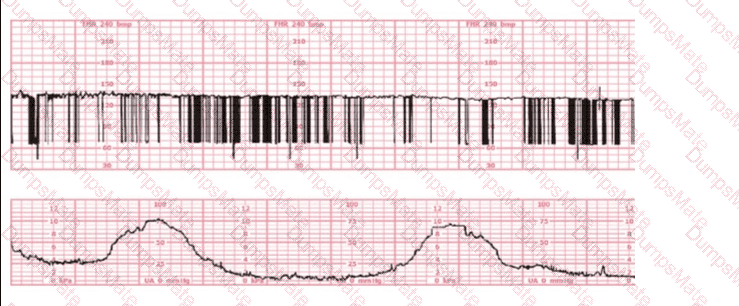

This fetal heart rate tracing is obtained upon the woman's admission to labor and delivery. This tracing is most reflective of:

EFM Question 5

Options:

A.

Atrial flutter

B.

Complete heart block

C.

Fetal dysrhythmia

Buy Now